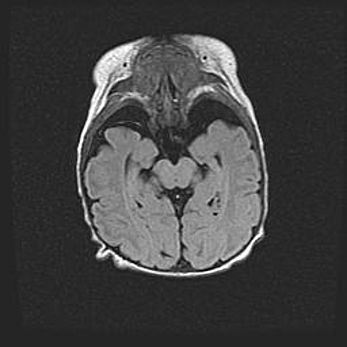

Аномалия Денди-Уокера. Признаки гипоплазии мозолистого тела.

Возраст: 5 месяцев 3 дня

Вес: 5550 г

Пол: мужской

Окружность головы: 39 см

Срок гестации: 40 недель

Аномалия Денди-Уокера – это порок развития головного мозга, для которого характерна триада симптомов: гипотрофия или аплазия червя мозжечка и/или полушарий мозжечка, расширение четвёртого желудочка с формированием ликворной кисты задней черепной ямки, гипертензионная гидроцефалия различной степени.

Гипоплазия мозолистого тела относится к дефектам внутриутробного этапа развития мозговой ткани, возникающим в процессе закладки структур головного мозга, что происходит на начальных этапах развития эмбриона.